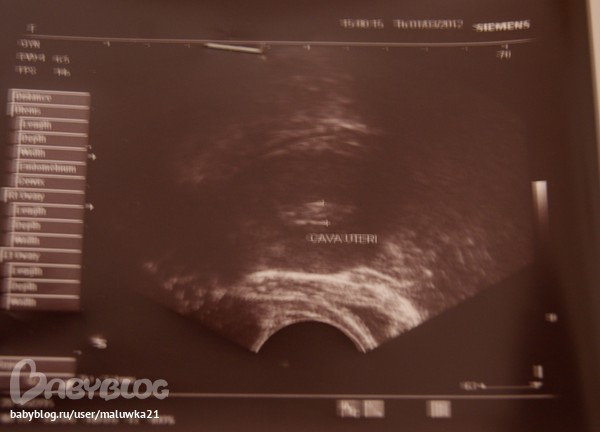

Результаты УЗИ:

матка с четкими недеформированными контурами.Размеры: 51,8х32,6х46,2мм.Шейка матки - толщина 23,4мм.Эндометрий неоднородный, толщина-5,1мм. (нашли какой то сгусток крови или полип(ниже кидаю фото))

извините за качество фоток,может что то поймете.Помогите розобратся,а то ничего не понимаю и не понимаю что ето может быть за полип...Благодарна за ответы...